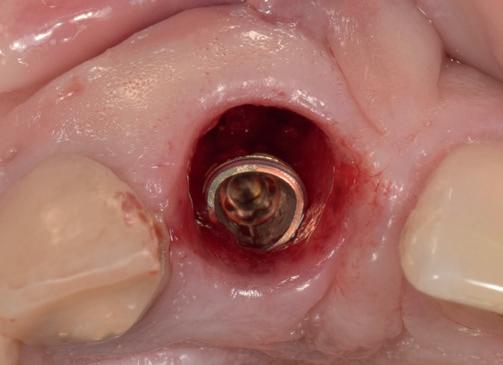

Tweede fase chirurgie

Na de genezingsperiode werd eerst een OPT röntgenopname vervaardigd om de genezing van de implantaten, kaakverbreding en sinusbodemelevatie te beoordelen. Er waren geen complicaties opgetreden. Bij de tweede fase chirurgie is het van absoluut belang dat er minimaal 2-3 mm gekeratiniseerd weefsel aan de buccale zijde van de implantaten wordt verkregen, anders kan de patiënt de implantaten niet goed reinigen en door de trekkrachten van de mucosa ontstaat al gauw peri-implantaire ontstekingen en recessies. De incisie hoeft niet van tuber tot tuber te zijn, maar 2 incisies van de 16 tot de 12 en 26 tot de 22 is voldoende, waarbij de incisie genoeg gekeratiniseerd weefsel aan de buccale zijde bevat, dat naar

de buccale zijde van de implantaten wordt geduwd. Er werden 6 healing abutments van 6 mm hoogte op de implantaten geplaatst, waarna de wonden werden gehecht met een 6-0 monofilament hechtdraad. In de prothese werd een nieuwe softliner over de healing abutments geplaatst. Het weefsel dient minimaal 4 weken genezingstijd te hebben (afbeelding 6).